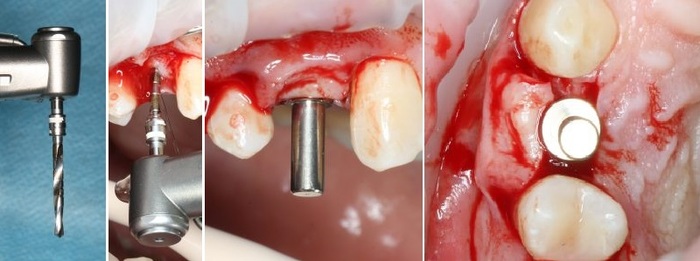

Теперь можно приступать к установке имплантата.

Имплантат нужного размера (3.8х11 мм) фиксируется на гексагональном ключе, после чего устанавливается в подготовленную лунку:

Еще раз проверяем поломжение имплантата:

Далее мы убираем временный абатмент, который в данном случае выполнял функцию имплантодержателя